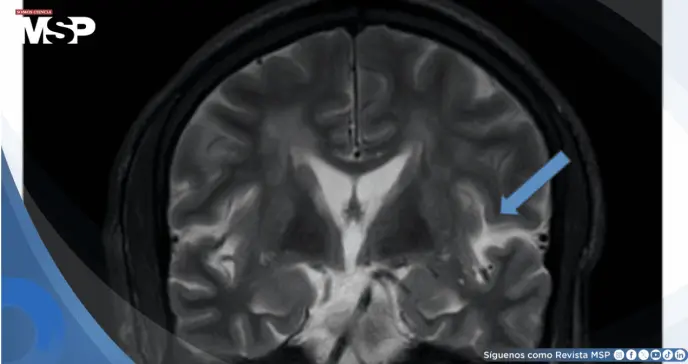

Se realizó resonancia magnética cerebral que demostró extensos parches de hiperintensidad en secuencias T2 y FLAIR distribuidos en el hemisferio cerebeloso izquierdo y regiones periventriculares y subcorticales bilaterales de ambos hemisferios, con predominio posterior.

Las secuencias de difusión (DWI/ADC) no mostraron restricción evidente. Las imágenes T1 con contraste revelaron realce leptomeníngeo parieto-occipital izquierdo. La angiorresonancia de vasos intracraneales descartó vasoespasmo, excluyendo el síndrome de vasoconstricción cerebral reversible.

Los hallazgos en resonancia magnética mostraron el patrón característico de edema vasogénico en regiones parieto-occipitales bilaterales.